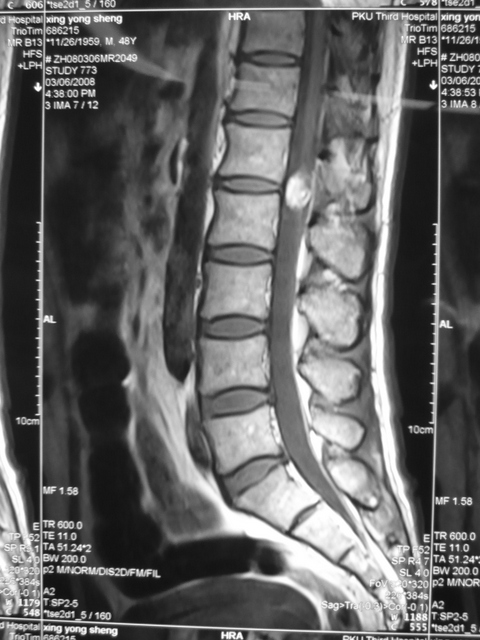

圆锥畸胎瘤